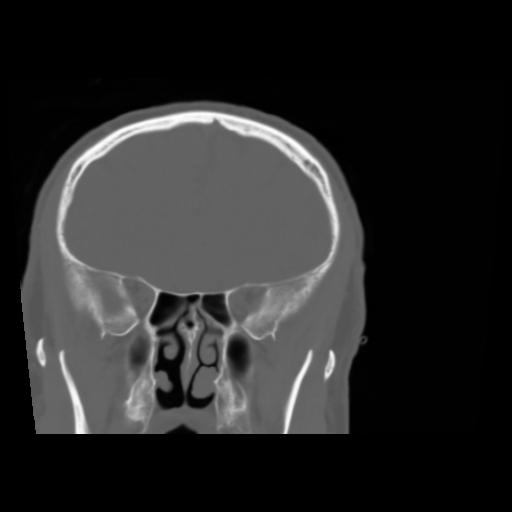

5 CEREBRO,,Coronal,3.000,CEREBRO,Coronal,